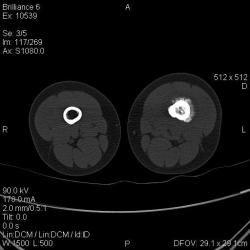

Мальчик 8 лет. Жалобы на боли в левом бедре. Со слов мальчика, ударился бедром несколько недель назад, после чего и начались боли. Выполнили рентгенограммы, затем - КТ (заранее прошу прошение за качество). Диагноз вроде сомнений не вызывает:(

Типичный анамнез, почти всегда упоминание о какой-нибудь, пусть даже малозначимой, травме. Да, ОНА - остеогенная саркома.

Я бы на первое место поставила саркому Юинга. У нас была девочка 5 лет, с подобными изменениями в бедренной кости, только чуть выше, гистологически была саркома Юинга.

Согласен со Шлевой. А дискуссии гасить (смайлы)! Картина достаточно характерная, диагноз более-менее ясен и без патоморфологического подтвержденния, тем более приличия соблюдены - не просто снимки, а снимки + КТ. Так что тем быстрее пациент окажется в специализиованном учреждении, тем лучше.